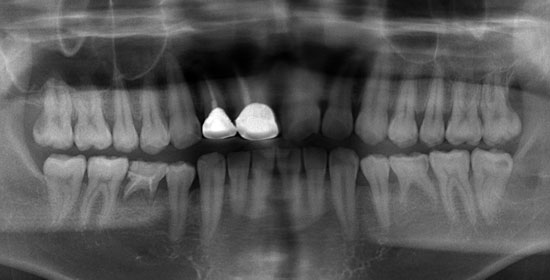

術前CT

二次元的なレントゲン画像では歯と下顎管の正確な位置をつかめない場合があります。CTを分析することにより、歯と下顎管の位置関係を正確に把握し、より安全に抜歯をすることが出来ます。

術後

安全に抜歯をすることが出来ました。当クリニックではなるべく腫れない切開法を行い、骨削除を最小限にすることで、術後の腫れや痛みを抑えた抜歯を行っております。